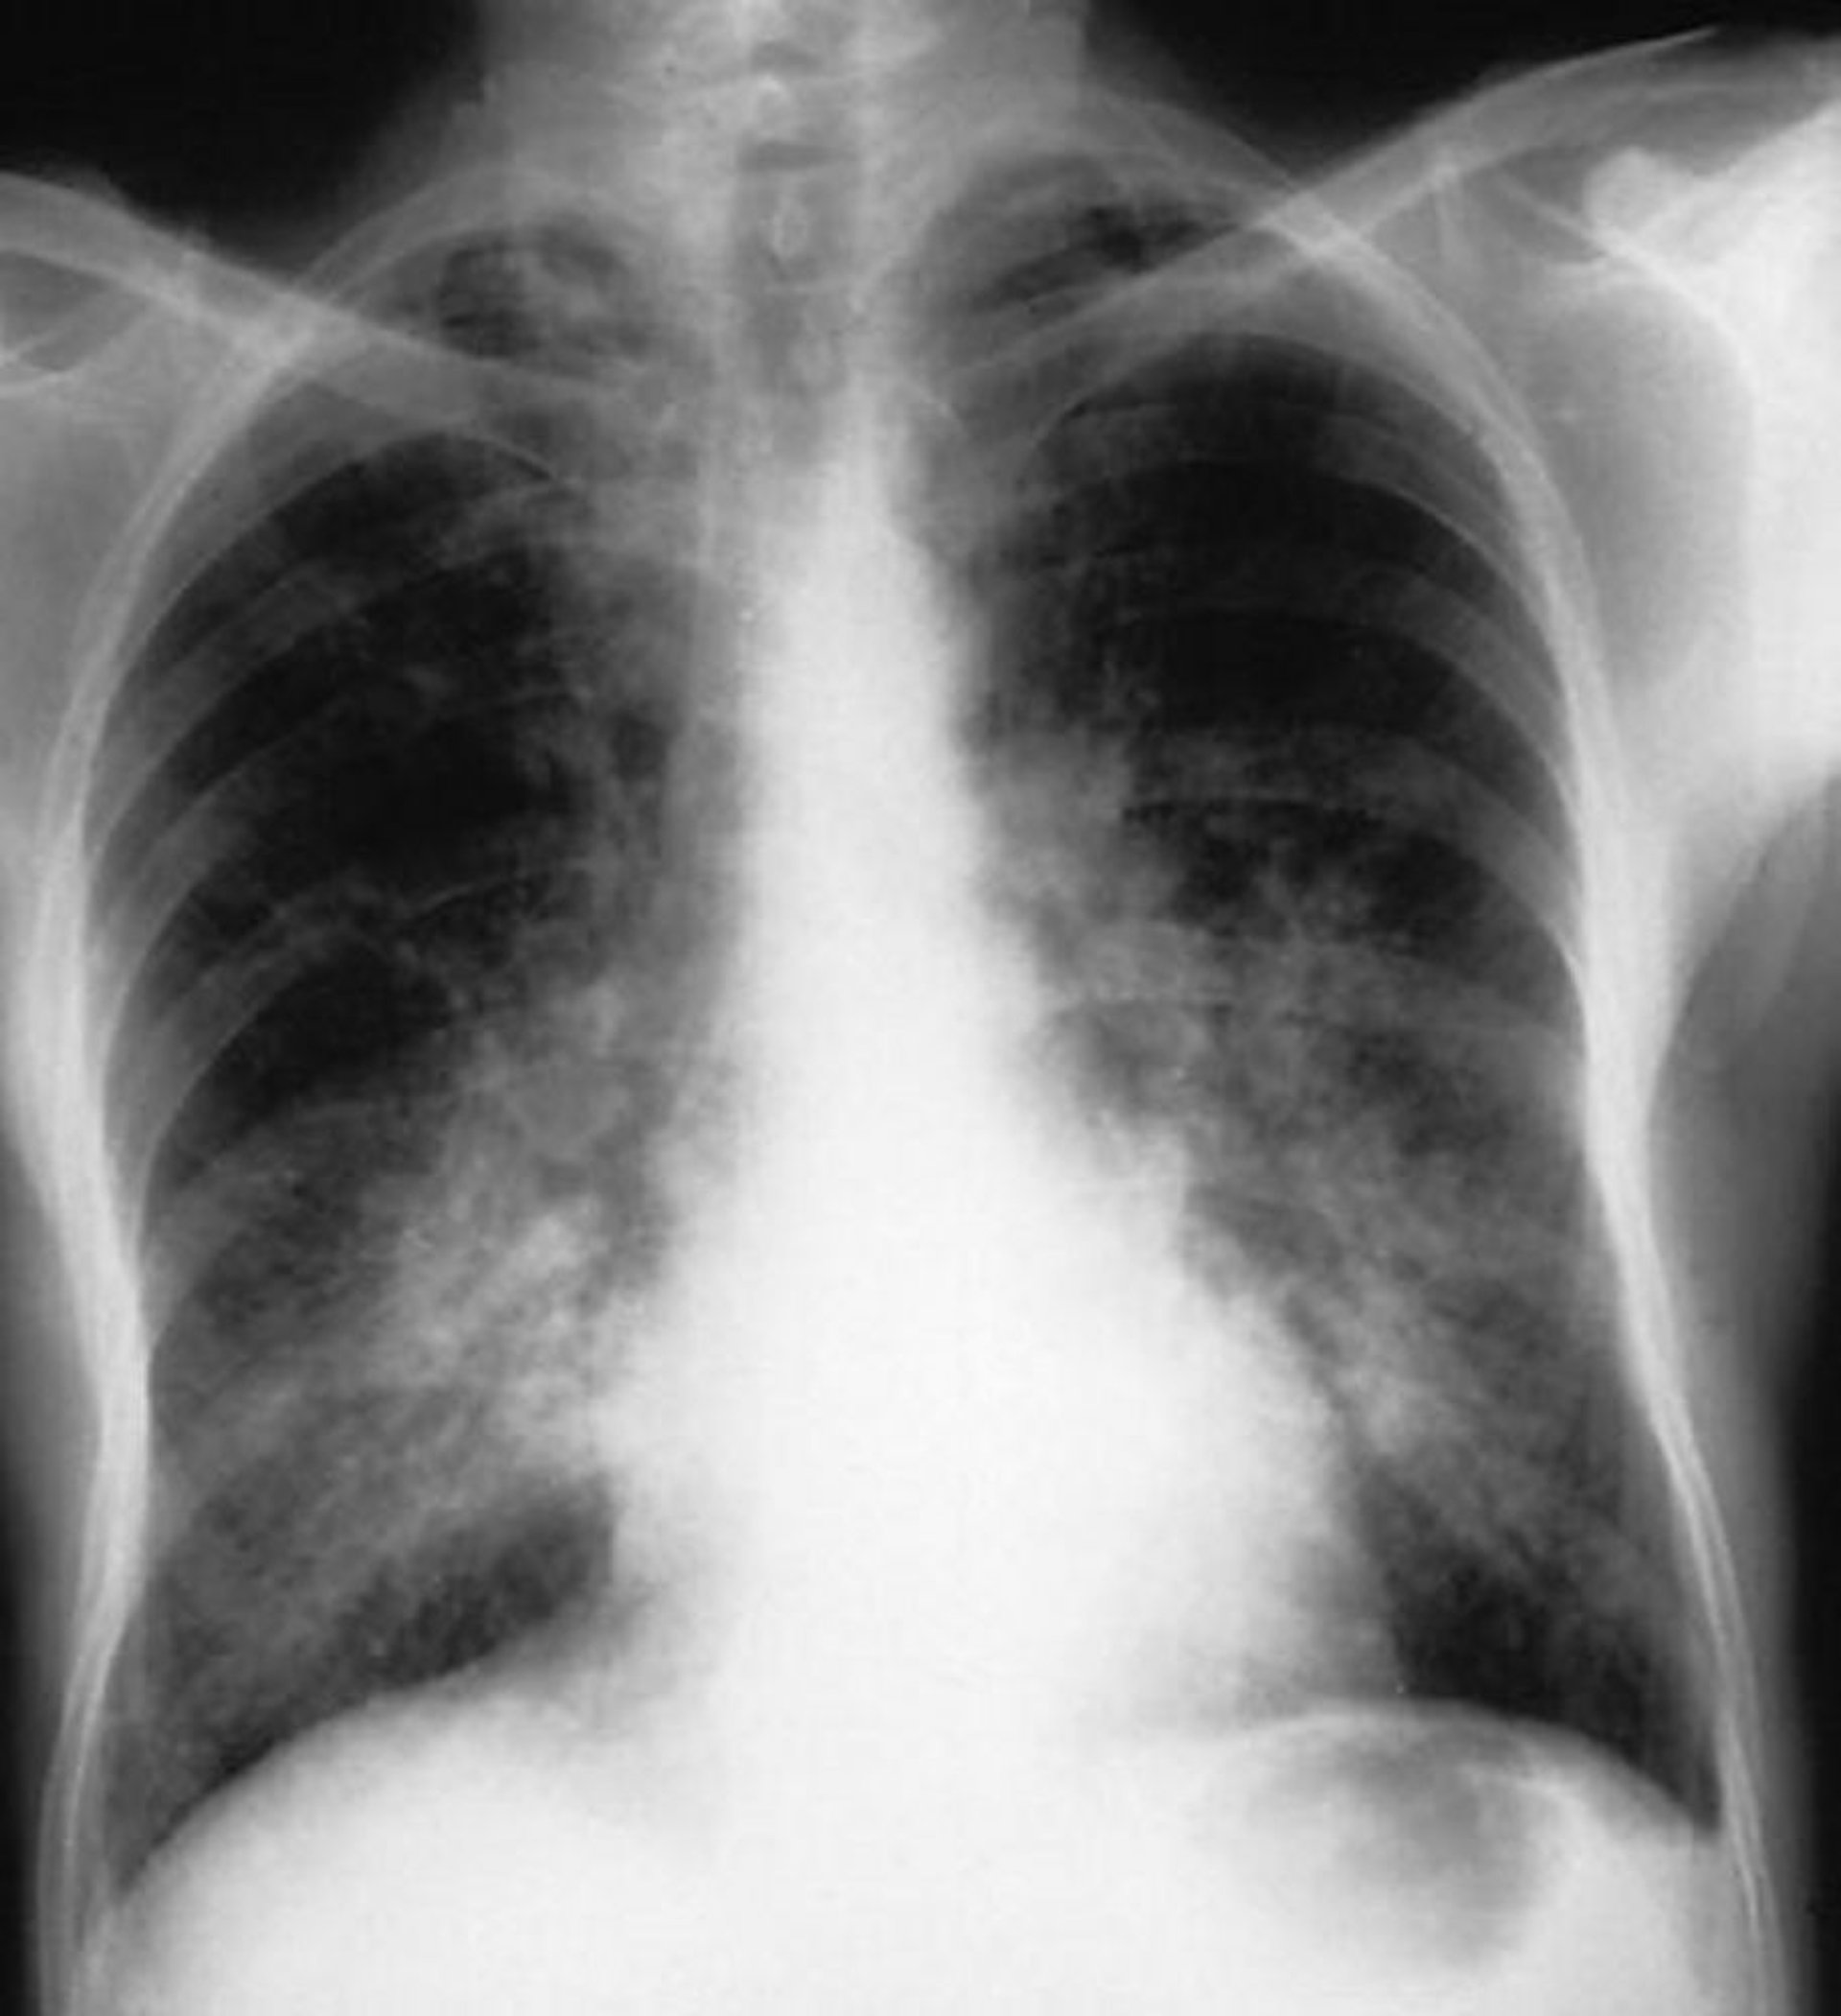

肺胞出血

この胸部X線像には,肺胞出血患者にみられた両側性の肺胞性陰影が示されている。